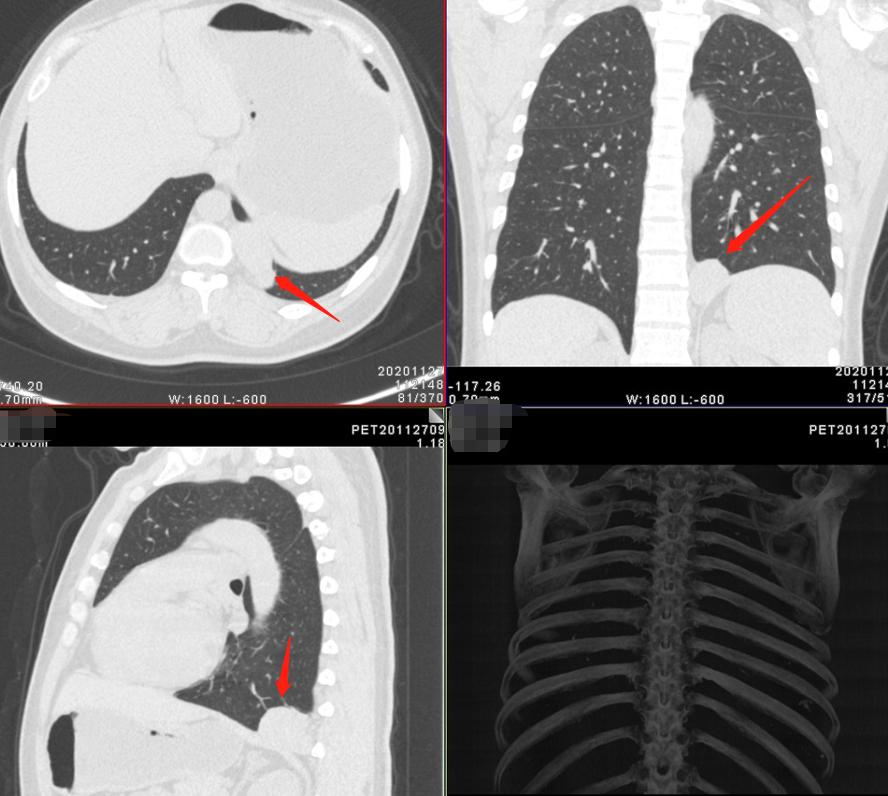

1:女性 47岁 体检发现右肺结节1周,预行手术,进行术前分期、评估。

薄层高分辨三维重组图片

妥妥的恶性征象,令人心惊胆寒

影像学检查特点:右肺上叶尖段实性结节,大小1.2cm×1.1cm×1.0cm,分叶毛刺、胸膜牵拉,最主要的是有两个大的引流血管汇聚,诊断为恶性病变还需要理由吗?不需要理由。这种征象哪个医生也不敢说一定是良性的。建议活检应该是最好的选择。